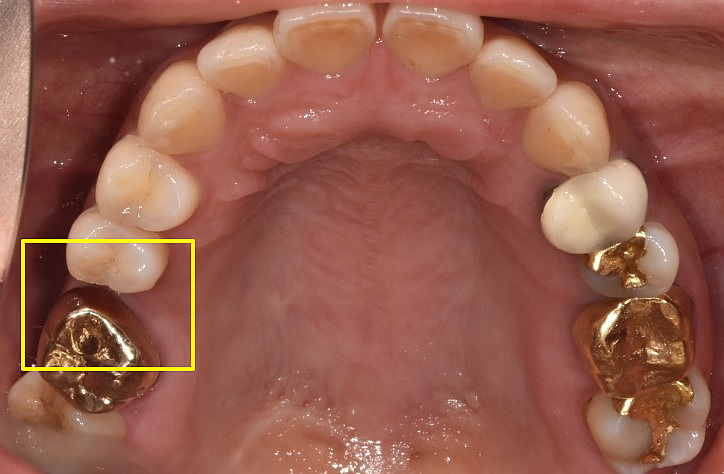

| 심각한 염증으로 발치후 임플란트 한 치료 사례 |

49세 남성

(전) 2021-12-28, (후) 2022-08-06

상기 환자분도 위 어금니 통증이 너무 심해서 내원하신 분으로, 파노라마 촬영상 치아 뿌리 끝에 심각한 염증이 관찰되었습니다.

또한 염증으로 인해 치아가 흔들리고 있던 상황이었기 때문에 발치 후 임플란트 시술을 고려할 수밖에 없었는데요.

특히 심한 염증으로 인한 치근낭(치아뿌리 끝에 물혹이 생긴 질환)이 관찰되어, 발치하면서 치근낭적출술도 함께 시행하였습니다.

치근낭은 대부분 증상이 없지만 낭종이 커지면서 부종이 생길 수 있고, 잇몸뼈가 녹아 치아가 흔들리게 할 수 있습니다.

그래서 환자분 케이스는 발치 후 즉시 식립이 어려워서 당일 뼈이식만 진행하고, 3개월 후 지연 식립을 진행하게 되었습니다.

염증이 워낙 심했던 케이스라 최종 보철물을 올리기까지 약 8개월 정도가 소요되었는데요.

이처럼 심각한 염증은 발치후 임플란트 기간을 지연시킬 수 있습니다. 그러니 미리미리 치과에 내원하셔서 정기검진받으시길 바랍니다.